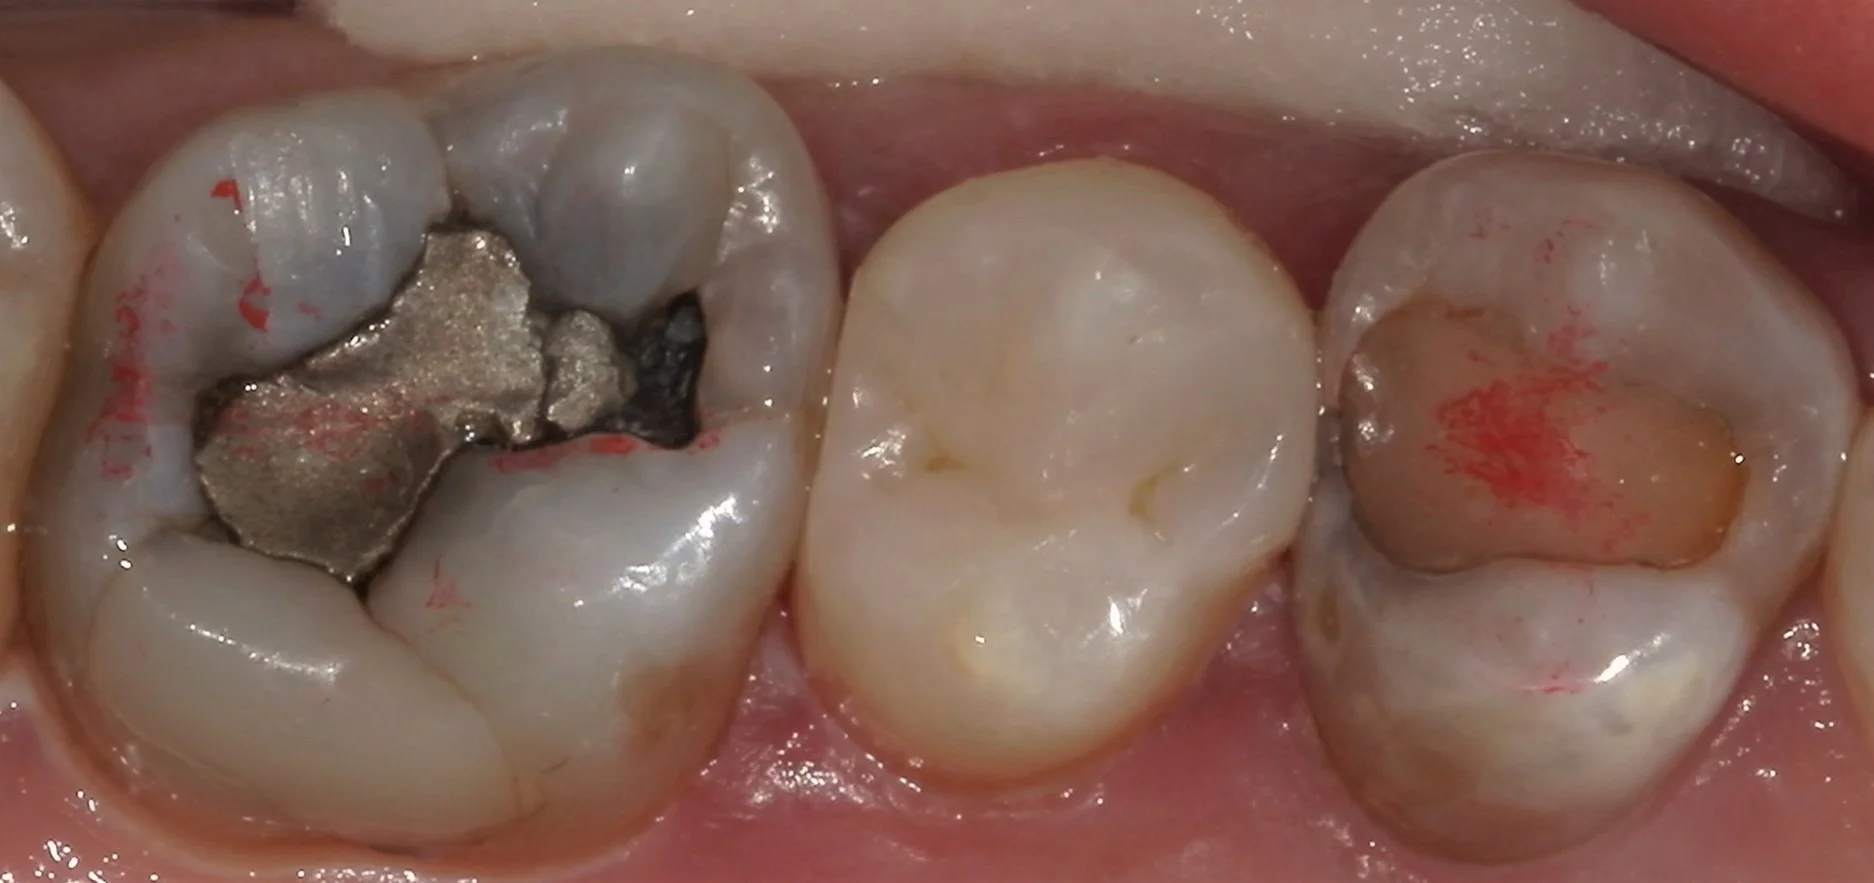

そして1カ月後・・・今度はその前後の歯の治療でお越しいただきました。

その時に虫歯を見やすくしたのが、こちらの写真です。

画面左側の歯はレントゲンで見るよりも遥かに内面で大きくなっていましたね。

そして画面右側の神経の治療の際に詰めるピンクの薬が見えている状態です。